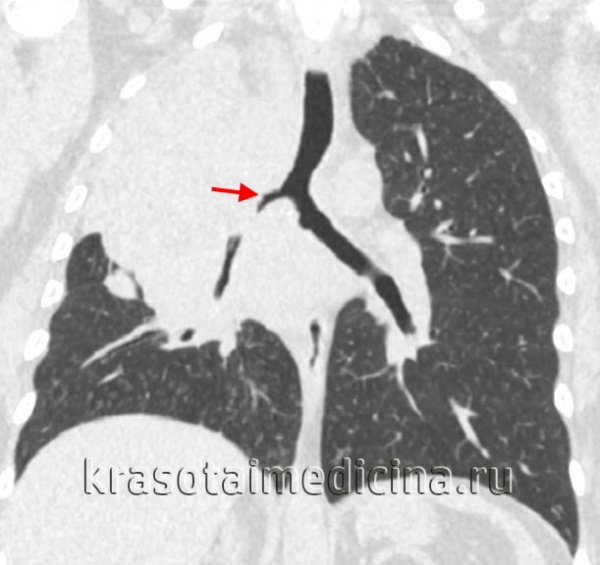

![КТ органов грудной клетки. Ателектаз верхней доли правого легкого, обусловленный злокачественной опухолью правого верхнедолевого бронха]()

КТ органов грудной клетки. Ателектаз верхней доли правого легкого, обусловленный злокачественной опухолью правого верхнедолевого бронха

Для выяснения причин обструктивного ателектаза легкого информативна бронхоскопия. При длительно существующем ателектазе, для оценки степени поражения производятся бронхография и ангиопульмонография. Рентгеноконтрастное исследование бронхиального дерева выявляет уменьшение участка ателектазированного легкого и деформацию бронхов. По данным АПГ можно судить о состоянии легочной паренхимы и глубине ее поражения. Исследование газового состава крови выявляет значительное снижение парциального давления кислорода. В рамках дифференциальной диагностики исключаются агенезия и гипоплазия легкого, междолевой плеврит, релаксация диафрагмы, диафрагмальная грыжа, киста легкого, опухоли средостения, крупозная пневмония, цирроз легкого, гемоторакс и др.